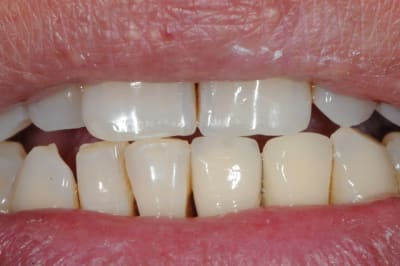

photo 1: début du cas

photo 2: fin d'intervention

photo 3: j+3mois

photo 4 +5: prise d'empreintes

photo 6-7-8-9: couronne finie.

merci de votre attention :)

PS: le patient ne veux pas faire celle d'à coté.

grr, moi ça me démange...